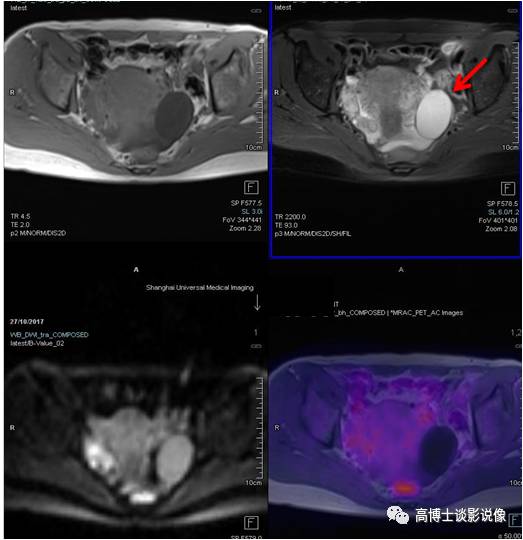

前列腺癌

老年男性,腹痛一周伴低热。PET/MR示前列腺左后方外周带见类圆形异常信号灶,直径约1.1cm,FDG摄取稍增高。之后穿刺证实为前列腺癌。

点评

前列腺癌高峰年龄是70~80岁,早期常无症状,血化验PSA升高,可以帮助筛查,但是有相当一部分前列腺炎症PSA也会升高,所以进一步鉴别需要依靠MRI/ PET,查出病变后还可以指导临床选择穿刺部位。

宫颈癌

中年女性,下腹部坠胀感1月。宫颈可见一类圆形软组织信号,大小约2.3cm× 2.5cm ,FDG摄取增高,病理诊断为宫颈鳞状细胞癌。

宫颈癌是最常见的妇科恶性肿瘤。高危型HPV持续感染是宫颈癌的主要危险因素。宫颈刮片细胞学检查是主要的筛查方法。PET对宫颈浸润癌的诊断准确性较高,对于术前分期和治疗后疗效评估很有价值。

子宫肌瘤

年轻女性,无明显不适。子宫后壁肌层可见一椭圆形异常信号灶,长径约3.3cm, FDG无代谢,诊断为子宫肌瘤。

子宫肌瘤是女性生殖系统中最常见的一种良性肿瘤。子宫肌瘤较小或者不位于黏膜下的,一般无症状,明显增大后会压迫膀胱等邻近脏器,或者造成月经量增多,甚至腹痛等不适。常规检查B超可以解决问题,PET/MR可以帮助鉴别子宫病变良恶性。治疗因人而异。

卵巢囊肿

年轻女性,无明显不适。左侧附件区见一长径约5.0cm椭圆形囊性信号灶,边界清楚,FDG未见明显摄取,考虑为卵巢囊肿。

PET/MR检查常常会发现卵巢囊性病变,多数为生理性囊肿(滤泡或黄体囊肿),均与女性内分泌功能相关,随着体内激素水平的变化而变化,因此发现此种卵巢囊肿后不必过分紧张,大于3cm者,建议B超定期随访复查。